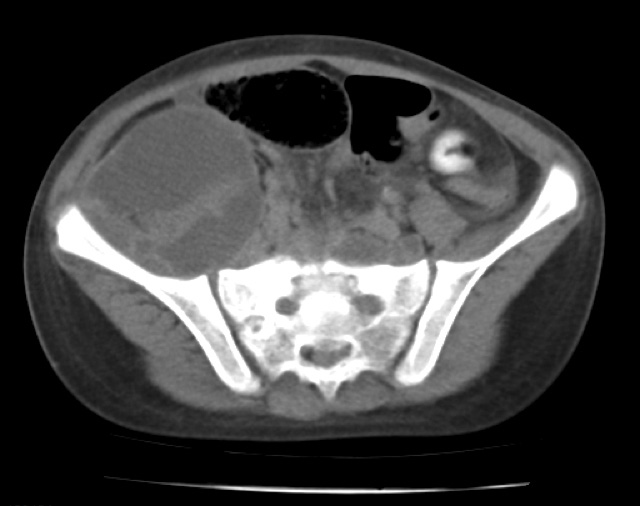

A partir de la tercera semana, la paciente presenta fiebre, malestar general y aumento en la intensidad del dolor propagándose a fosa iliaca derecha; consulta al hospital de su localidad donde deciden internarla; le realizan un hemograma que muestra leucocitosis con neutrofilia y una ecografía abdominal que evidencia una lesión heterogénea, hipoecoica, con septos en su interior y bordes irregulares en músculo psoas derecho. Se hace tomografía computarizada (TC) de abdomen mostrando contenido hipodenso retroperitoneal en psoas derecho con extensión hacia fosa iliaca derecha y región pélvica, se plantea posible absceso o tumor retroperitoneal (Figura 1).

Figura 1. TC: absceso del psoas derecho. Fuente: Documento obtenido durante la realización del estudio.